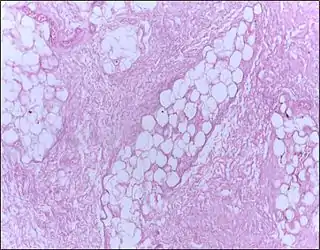

![]() Micrografía de tejido mamario que muestra necrosis grasa. Tinción Hematoxilina-Eosina | ||

La necrosis grasa es una forma de necrosis caracterizada por la acción de enzimas digestivos sobre la grasa.[1]

En la necrosis grasa el enzima lipasa libera ácidos grasos de triglicéridos. Entonces, los ácidos grasos se combinan con calcio para formar jabones. Estos jabones aparecen como depósitos calcáreos blancos.[2]

Normalmente está asociado con trauma del páncreas o pancreatitis aguda.[2][3] También puede ocurrir las mamas,[4] las glándulas salivales[5] y en neonatos después de un parto traumático.[cita requerida]